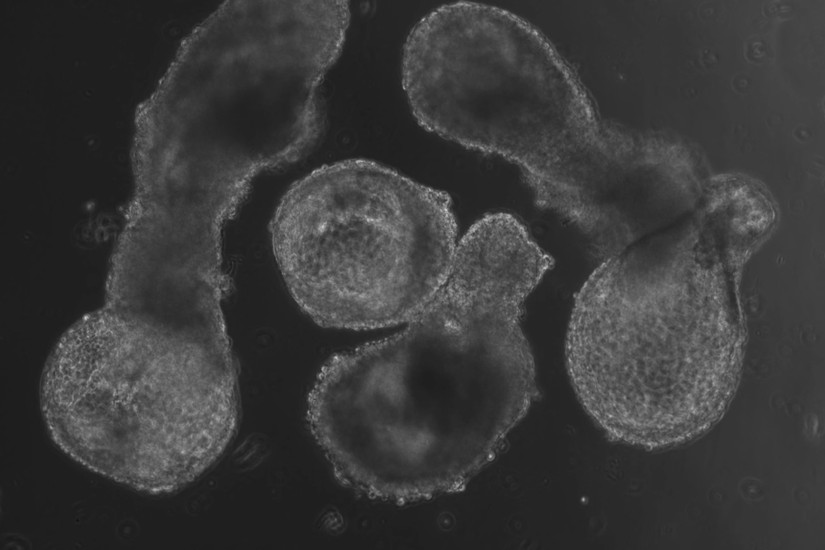

Naukowcy z Uniwersytetu w Cambridge ogłosili opracowanie w laboratorium struktury przypominającej wczesny ludzki zarodek, nazwaną hematoid. Model powstał z ludzkich komórek macierzystych, co budzi poważne pytania etyczne i moralne. Postęp naukowy nie może odbywać się kosztem życia ludzkiego ani godności osoby od poczęcia.

Odkrycie, zostało opisane w prestiżowym czasopiśmie Cell Reports i pozwoliło odtworzyć pierwsze etapy rozwoju człowieka, zwłaszcza moment, w którym zaczyna się wytwarzanie krwi.